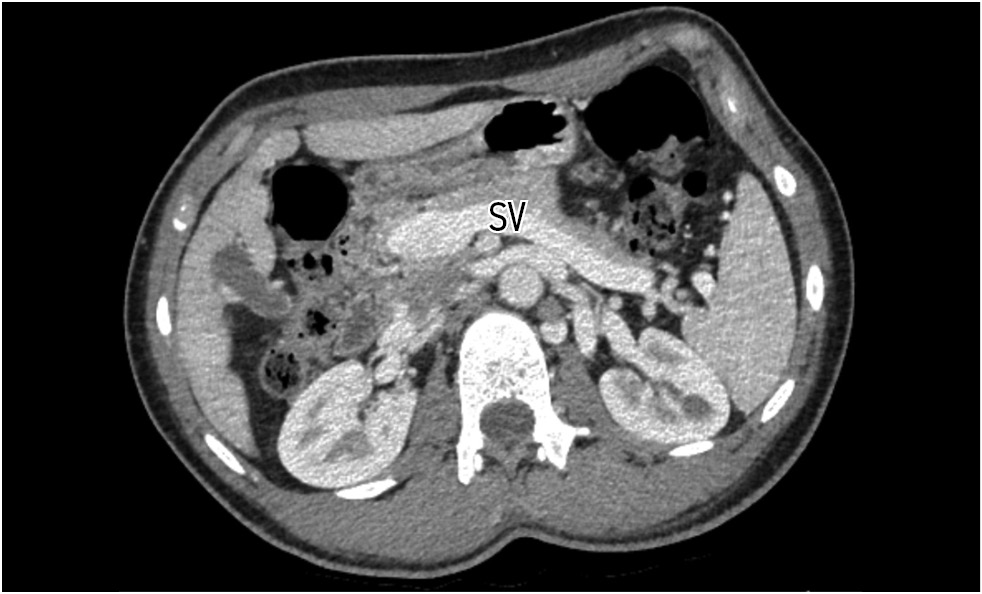

Contrast-enhanced abdominal computed tomography (CT) with multiplanar reconstruction revealed that the splenic (12 mm in diameter (Figure 1)) and superior mesenteric veins fused together, forming a portal vein conduit dilated to 28 mm in diameter (Figures 2 and 3), flowing directly into the inferior vena cava (IVC), bypassing the porta hepatis (Figure 4). Moreover, moderate liver and spleen enlargement and weak heterogeneous contrast enhancement of the liver parenchyma were noted. The findings were consistent with Abernethy malformation type Ib.

Fig. 1. Contrast-enhanced CT, portal phase, axial view. Dilated splenic vein (SV).